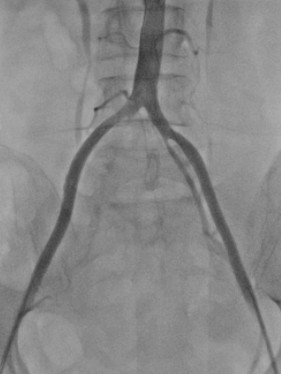

經(jīng)過(guò)CTA證實(shí),伊女士出現(xiàn)的是腹主動(dòng)脈騎跨栓,從腹主動(dòng)脈下段分叉開(kāi)始都出現(xiàn)了不同程度的栓塞,雙下肢出現(xiàn)了嚴(yán)重的缺血。

圖中箭頭所示:術(shù)前CTA提示腹主動(dòng)脈雙髂動(dòng)脈騎跨栓,腹主動(dòng)脈下段及雙髂動(dòng)脈血流中斷